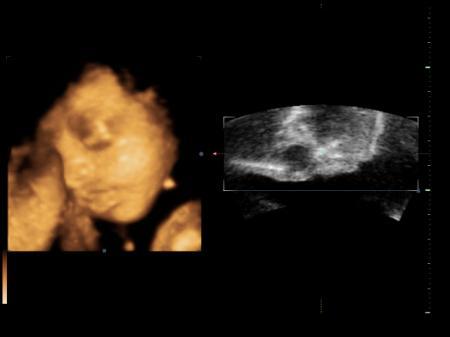

Soooooooooooooooooooo guten Morgen, @Ari 25: Ich habe unter meinem Beitrag von gestern geantwortet, ob die Ex sich noch mal gemeldet hat!!! Die Antwort : Ja! :) Danke an den Rest für eure Antworten, haben mich ein wenig beruhigt, werde wohl zur Apo gehen und mir dieses Planktur20 gegen Haarausfall holen und meine Haare nicht mehr so doll mit heißer Fönluft und tupieren reizen. Und jetzt zu meinem kleinen, persönlichen Star. War gestern ja beim Ultraschall. Die Kleine wiegt genau 1000gr und ist ca. 35cm groß! Ab heute kann ich auch groß 8ter Monat schreiben!!!!! Leider, hatte sie die Hand vor dem Gesicht beim 3D Bild machen und der Arzt meinte, dass sie noch ein wenig zu dünn sei und sich noch was anfuttern muss, damit man bessere Bilder bekommt. Soll in zwei-drei Wochen noch mal hin. Musste das 3D dann auch nicht bezahlen, habe aber trotzdem ein, zwei Bilder mitbekommen und bin verliebt. Ehrlich gesagt, finde ich das schon toll, wenn man sein Schatz sieht und sich selber darin erkennt. Sie hat mein Gesicht, aber Papas schöne Lippen! Kleiner Schmollmund!!! Ich lade es mal hoch! Ich liebe sie sooooooo!!! Happy Mom Jasmin :)

Bild zu Unser Engelchen - Forum für April - Mamis